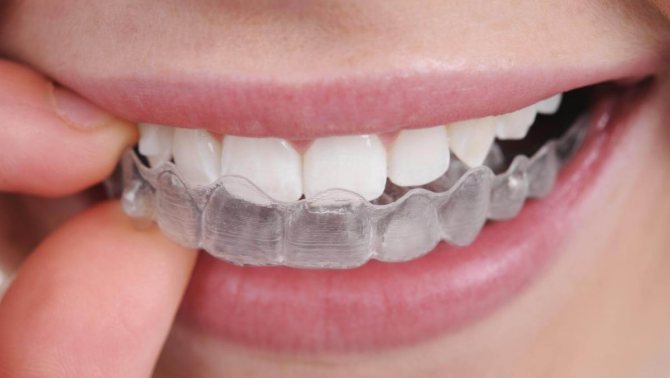

Эластопозиционеры используются лишь в случае небольшого отклонения. Их можно охарактеризовать как двухчелюстные капы с каналами для зубов и лабиальными дугами. Стабилизация работы мышц выступает дополнительной функцией. Пластины нужно надевать перед сном и носить в дневное время на протяжении двух часов.